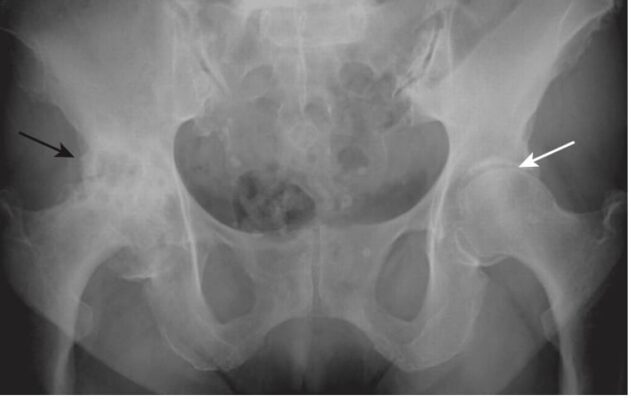

Hình 7. Thoái hóa khớp thứ phát ở khớp háng phải. Có sự khác biệt rõ rệt giữa hai khớp háng: trong khi háng bên phải bị thoái hóa khớp nặng (mũi tên đen) thì khớp háng bên trái tương đối bình thường (mũi tên trắng). Bệnh nhân này bị trượt chỏm xương đùi (SCFE) bên phải và chưa từng được chăm sóc điều trị.